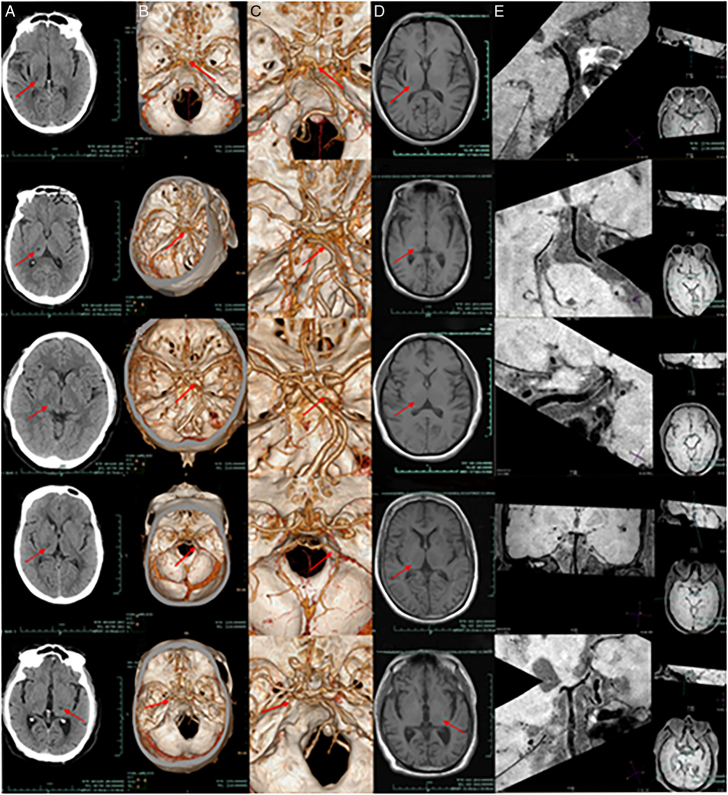

Introduction: Ten patients with thalamic infarction caused by moderate-to-severe posterior cerebral artery (PCA) stenosis confirmed by computed tomography angiography (CTA) were enrolled. To better assess the vascular pathology, high-resolution magnetic resonance imaging (HRMRI) was subsequently used to evaluate the PCA in detail. In addition, we retrospectively analyzed clinical features, treatments, and prognostic outcomes.

Case report: Ten patients were included, 7 males and 3 females, with an average age of 67.8±6.6 years. Past history includes: smoking (50%), drinking (30%), hypertension (70%), diabetes mellitus (40%), hyperlipidemia (10%), and cerebral infarction (10%). Clinical manifestations include sensory disorders (60%), motor disorders (50%), cognitive and consciousness disorders (10%), and language impairment (20%). HRMRI suggested that the PCA was moderately or severely stenosed in 4 cases, mildly stenosed in 5 cases, and normal in 1 case. It also suggested the presence of PCA atherosclerotic plaques in 9 patients.

Conclusion: Antiplatelet therapy proves effective for this patient population. HRMRI identified atherosclerotic plaques mainly in the PCA's P1 and P2 segments. P1 stenosis often impairs consciousness, while P2 stenosis typically causes sensory/motor deficits. HRMRI aids in evaluating stenosis and plaque features for diagnosis and treatment guidance.